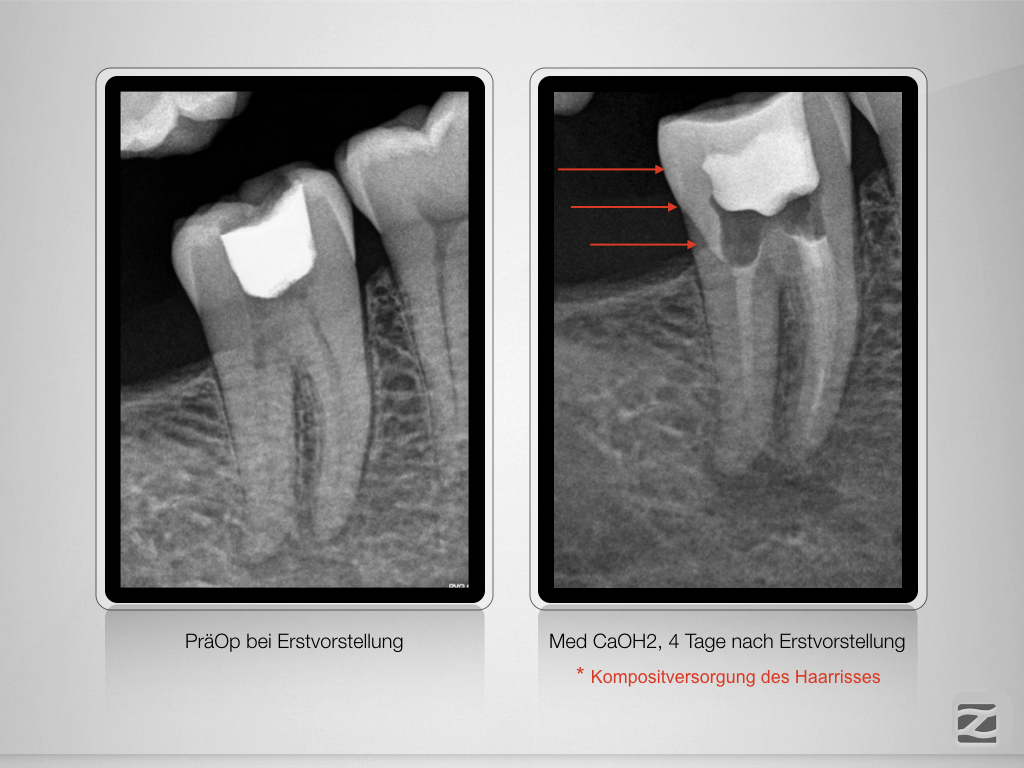

46D.004 Veröffentlicht 27. November 2019 am 1024 × 768 in Sensibilitätsstörung nach Initialbehandlung